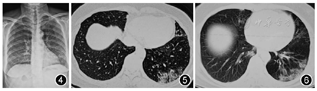

例1 男,68岁,湖北省秭归县人。因"发热、流涕、眩晕不适3 d",发病后自测体温最高达38.2 ℃,曾于2020年1月26日在天水市第四人民医院发热门诊就诊,于1月29日收住定点救治单位天水市第二人民医院感染科。患者于1月3日从湖北宜昌回到天水市,期间无明显不适。曾与2020年1月20日由武汉返回天水市的亲属有密切接触史,该亲属后被确诊为新型冠状病毒肺炎。入院查体:体温37.3 ℃。咽部红肿,双肺呼吸音粗。2020年1月29日血常规示白细胞计数为5.09×109/L,淋巴细胞计数为0.81×109/L。2020年2月5日血常规示白细胞计数为4.91×109/L,淋巴细胞计数为0.64×109/L,C反应蛋白为41.2 mg/L,降钙素原为0.37 μg/L。动脉血气分析(未吸氧)PaO2为63 mmHg(1 mmHg=0.133 kPa),PaCO2为36 mmHg,氧合指数为300 mmHg。2020年2月7日血常规示白细胞计数为8.1×109/L,淋巴细胞计数为1.07×109/L。动脉血气分析(未吸氧)示PaO2为58 mmHg,PaCO2为38 mmHg,氧合指数为276 mmHg。发病早期X线胸片提示双肺纹理增粗(图1),随病程进展胸部CT呈现典型的病毒性肺炎征象(图2,图3)。

先后4次咽拭子核酸检测均为阴性,给予高渗盐雾化诱导排痰后痰标本送新型冠状病毒核酸检测阳性,氧合指数为276 mmHg,确诊为新型冠状病毒肺炎重型。